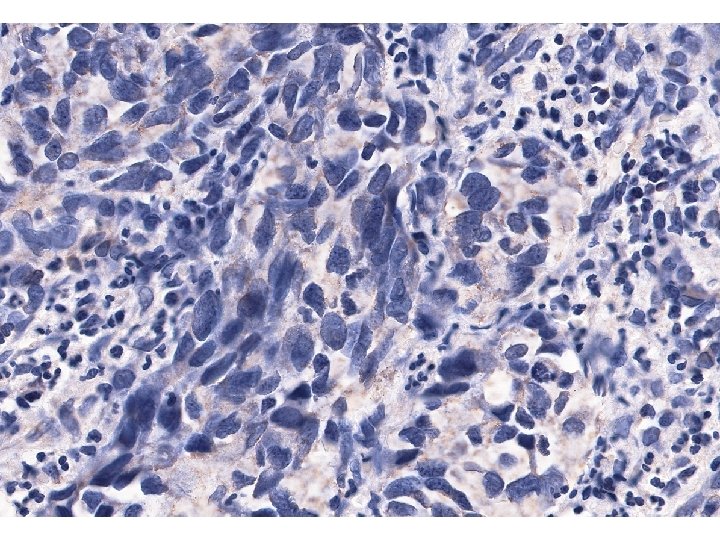

Imunohistologický nález nádorových buněk • K vyloučení nediferencovaného karcinomu vyšetřeny cytokeratiny, skupinovitě (AE 1/AE

Imunohistologický nález nádorových buněk • K vyloučení nediferencovaného karcinomu vyšetřeny cytokeratiny, skupinovitě (AE 1/AE 3), i jednotlivě, reakce nádorových buněk bylanegativní. • Také reakce na CD 117 na možný stromálmí nádor byla negativní. • Reakce na S 100 protein byla slabá, ale zřetelně pozitivní, silně pozitivní reakce byla na Melan A i na HMB 45.

Diagnostický závěr • Pozitivní reakce na Melan A a na S 100 protein svědčí

Diagnostický závěr • Pozitivní reakce na Melan A a na S 100 protein svědčí pro dg. maligního melanomu, negativní reakce na cytokeratiny a CD 117 vyloučily nediferencovaný karcinom a maligní stromální tumor. • Je tento nádor primární?